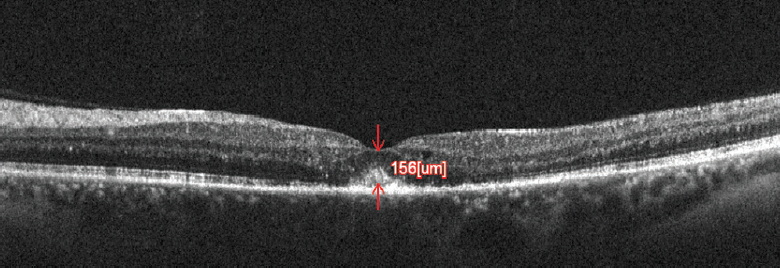

<p>Figure 2. A good response was seen at 1 month after the patient’s first anti-VEGF injection. OCT shows reduction in CME with CMT of 156 μm.</p>

Figure 2. A good response was seen at 1 month after the patient’s first anti-VEGF injection. OCT shows reduction in CME with CMT of 156 μm.

At 1 month follow-up, OCT showed reduction in CMT to 156 µm (Figure 2). BCVA had improved to 10/20 in the left eye. Two months later, OCT showed recurrence of edema with CMT of 702 µm, and a second injection of bevacizumab was given (Figure 3).